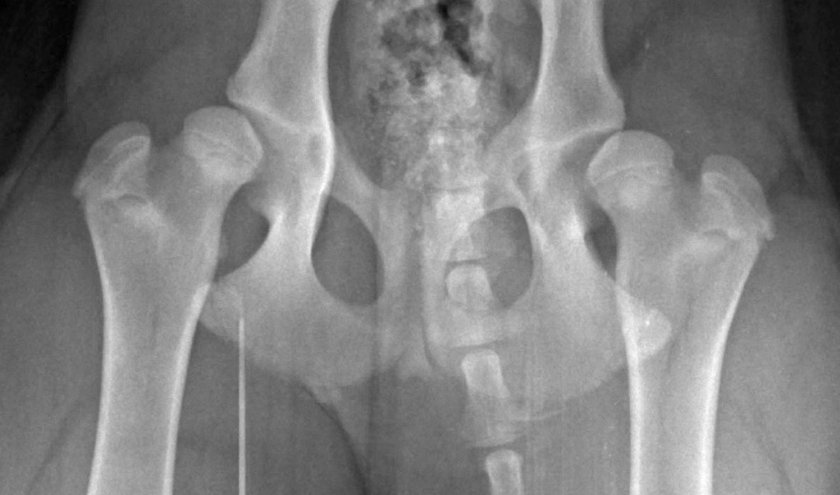

Диагноз «дисплазия тазобедренного сустава» никогда не ставится «на глаз». Получив рентгенографические снимки, ветврач проводит детальные расчёты, вычисляя соответствие поверхности вертулужной впадины и головки бедренной кости собаки, тангенциальный угол и индекс внедрения кости во впадину. Вместе с тем оценивается её форма и строение, ширина и равномерность щели сустава, а также подтверждается отсутствие хирургического вмешательства для улучшения изначальных характеристик.

Достоверность результатов исследования напрямую зависит от спокойствия и максимального расслабления собаки, поэтому через внутривенный катетер ей вводится седативное средство. После этого питомца кладут на спину с вытянутыми параллельно конечностями и делают снимок правой и левой стороны.

Чтобы полученные снимки могли послужить доказательством отсутствия проблем с суставами, они должны отвечать нескольким основным требованиям:

- показывать чёткие контуры костей и их архитектуру, в том числе верхний край вертлужной впадины;

- отображать тень таза и коленных суставов, причём так, чтобы изображение левого и правого подвздошного гребня находились на одном уровне, а тени чашечек колен располагались напротив блока.